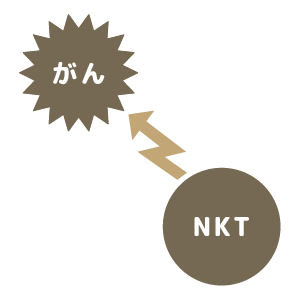

従来の免疫療法は、がんを標的として、がんを攻撃する免疫細胞を増やすという手法でした。攻撃部隊となるNK細胞やT細胞といった免疫細胞を体外で培養し、数を増やしてから体に戻す治療方法がとられます。しかし、この方法では以下のようなさまざまな理由で、十分な治療効果は得られませんでした。

- がん細胞の生残りや変異があり、がん細胞をすべて死滅させることができない

- 体に戻した免疫細胞には寿命があり、効果が持続しない。

- 免疫細胞ががん組織に到達できない場合も多い。

- がん組織が免疫不全状態になっていて、免疫細胞本来の力を発揮できない